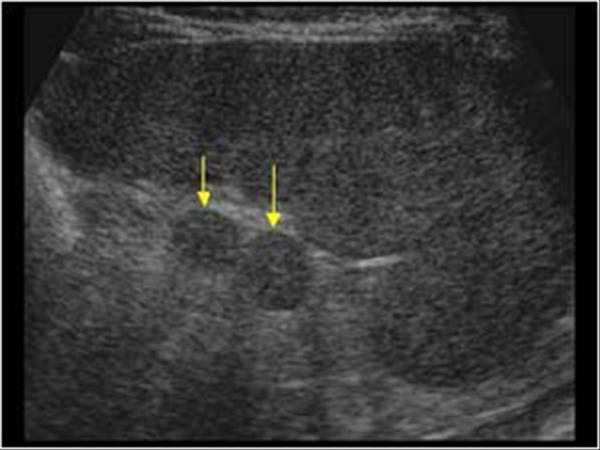

Pancreatic Psydocyst

Spherical fluid collection of pancreatic enzymes that arise from inflamatory, necrotic and hemorrhage processes of the pancrreas

persistently elevated amylase and lipase

Pancreatic Psydocyst

Spherical fluid collection of pancreatic enzymes that arise from inflamatory, necrotic and hemorrhage processes of the pancrreas

persistently elevated amylase and lipase

Pancreatic Psydocyst

Spherical fluid collection of pancreatic enzymes that arise from inflamatory, necrotic and hemorrhage processes of the pancrreas